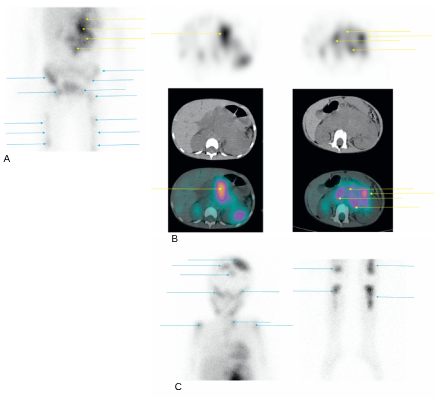

Fig. 105.5 Scintigraphie à la 123I-MIBG d’un enfant de 4 ans présentant un neuroblastome surrénalien gauche.

La volumineuse masse tumorale abdominale fixe la 123I-MIBG. Les images planaires mettent en évidence plusieurs hyperfixations du squelette en faveur de localisations secondaires. A. Image planaire, vue antérieure centrée sur l’abdomen, le bassin et les cuisses. B. images axiales tomoscintigraphiques couplées TDM centrées sur l’abdomen (flèches jaunes). C. Images planaires vue antérieure centrées sur le crâne et le thorax et sur les jambes, (flèches bleues).

Source : CERF, CNEBMN, 2022.